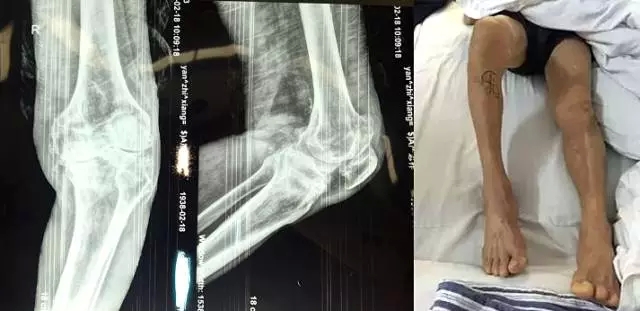

“嚴(yán)老伯的右膝患有重度關(guān)節(jié)骨性關(guān)節(jié)炎,右膝內(nèi)翻畸形,如果再晚點(diǎn)來(lái)就醫(yī),他的狀況還會(huì)持續(xù)變壞。”危立軍替嚴(yán)老伯仔細(xì)檢查之后說(shuō),“鑒于他的情況,我們建議實(shí)行人工膝關(guān)節(jié)表面置換術(shù)。”

2月26日,嚴(yán)老伯在廣安醫(yī)院關(guān)節(jié)科做了膝關(guān)節(jié)表面置換手術(shù),從切開(kāi)到縫合結(jié)束僅花了一個(gè)半小時(shí)。手術(shù)全過(guò)程病人基本上沒(méi)有手術(shù)后切口疼痛感,出血量不到150ml。術(shù)后第二天,他的右腿就能伸直了。

今天上午,主治醫(yī)生危立軍巡查病房時(shí)說(shuō):“嚴(yán)老伯的手術(shù)很成功,病人是非常嚴(yán)重的屈曲攣縮并內(nèi)翻畸形,膝關(guān)節(jié)平臺(tái)內(nèi)側(cè)骨缺損很嚴(yán)重。但我們采取了目前國(guó)際上最先進(jìn)的手術(shù)方法,無(wú)痛化病房管理和快速康復(fù)理念,所以病人恢復(fù)很快。”

據(jù)了解,以前像做這樣的手術(shù),病人大概需要休息兩個(gè)月左右才能逐漸康復(fù),而采取新的手術(shù)方法,按照嚴(yán)老伯目前恢復(fù)的情況,不需要什么特殊康復(fù),一周左右就能下地行走,兩周后就能出院。嚴(yán)老伯和家人對(duì)這次手術(shù)也表示非常滿意,他的關(guān)節(jié)內(nèi)翻也恢復(fù)到正常人一樣。